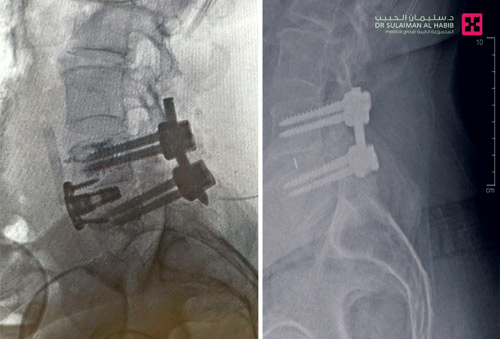

عمليتان تعيدان «سبعينياً» لحياته الطبيعية بمستشفى الدكتور سليمان الحبيب بالقصيم

أجرى مستشفى الدكتور سليمان الحبيب بالقصيم عملية تصحيحية دقيقة وناجحة أنهت معاناة مريض في العقد السابع سبق أن خضع لعملية تثبيت للفقرات القطنية الرابعة والخامسة قبل سنوات في أحد المستشفيات، وعانى لفترة طويلة من آلام حادة في منطقة أسفل الظهر تمتد للأطراف السفلية مما تسبب في الحد من حركته وأثر على نمط حياته.